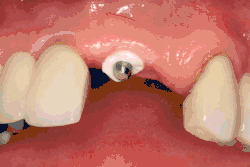

Основная операция по имплантации

Разборный имплантат состоит из непосредственно имплантата и надстройки (супраструктуры), именуемой абатментом. Такой имплантат может быть установлен по одно- и двухэтапному протоколу. Двухэтапный протокол подразумевает полное погружение имплантата и накрывание его слизистой оболочкой, в результате чего исключается любой контакт имплантата с полостью рта — эта процедура называется первым этапом дентальной имплантации. Второй этап заключается в установке какой-либо надстройки (супраструктуры) — это может быть как формирователь десны, так и абатмент с временной коронкой или другим видом протезной конструкции. После какого промежутка времени будет выполнен второй этап обычно решает имплантолог, опираясь на данные о качестве костной ткани, возраст и общее состояние пациента, а также свой клинический опыт. Классические сроки составляют 4—6 месяцев, однако последнее время существует тенденция к сокращению сроков ожидания до 2,5—3 месяцев. Это связано с лучшим пониманием процесса остеоинтеграции, а также оптимизацией макродизайна и микрохарактеристик поверхности имплантатов.

В неразборном имплантате (употребляются также термины: одноэтапный имплантат, моноимплантат) внутрикостная часть имплантата и абатмент обычно изготовлены из единого куска материала. После установки имплантат своей наддесневой частью сразу оказываются в контакте с полостью рта. На усмотрение доктора устанавливается формирователь десны либо временная коронка. В случае установки временной протезной конструкции (коронки, моста или полного протеза) на имплантат не позднее трёх дней после имплантации говорят о немедленной нагрузке.